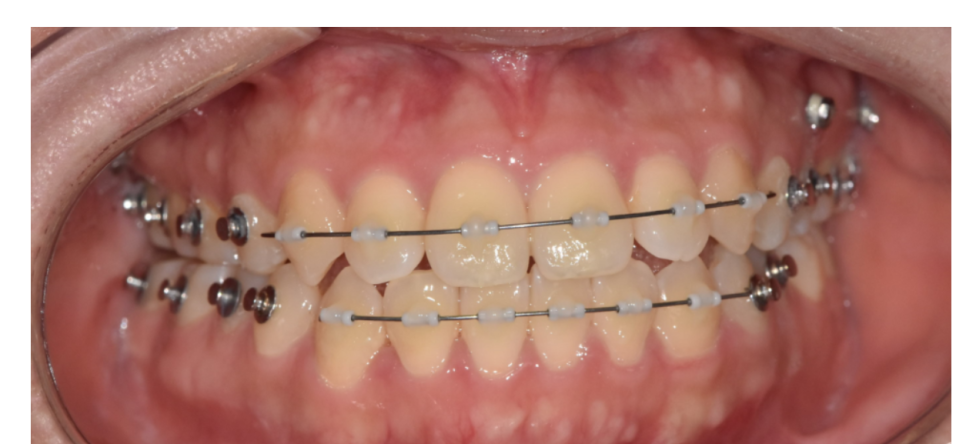

250116

250304

250509